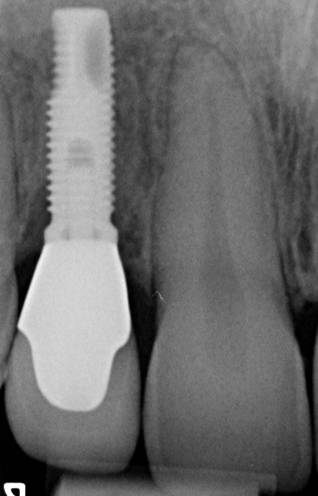

Gli impianti dentali sono protesi fisse composte da due elementi:

Vite Endossea - Vite in titanio che il dentista inserisce nell’osso alveolare dove era presente il dente da sostituire. Questa svolge la funzione di radice su cui sarà applicata la protesi dentale;

Protesi Dentale - Elemento in ceramica che il dentista ancora alla vite endossea. La protesi dentale ha lo stesso aspetto del dente e lo sostituisce nella sua totalità, conferendo al paziente un nuovo sorriso.